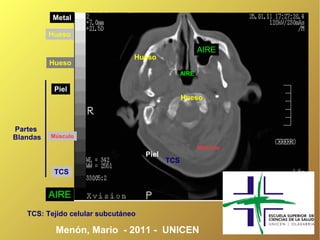

Metal

Hueso

AIRE

Piel

Partes

Blandas   Músculo

Músculo

TCS

TCS: Tejido celular subcutáneo

Menón, Mario - 2011 - UNICEN

Metal Hueso AIRE Hueso Hueso AIRE Piel Hueso Partes Blandas Músculo Músculo Piel TCS TCS AIRE TCS: Tejido celular subcutáneo Menón, Mario - 2011 - UNICEN